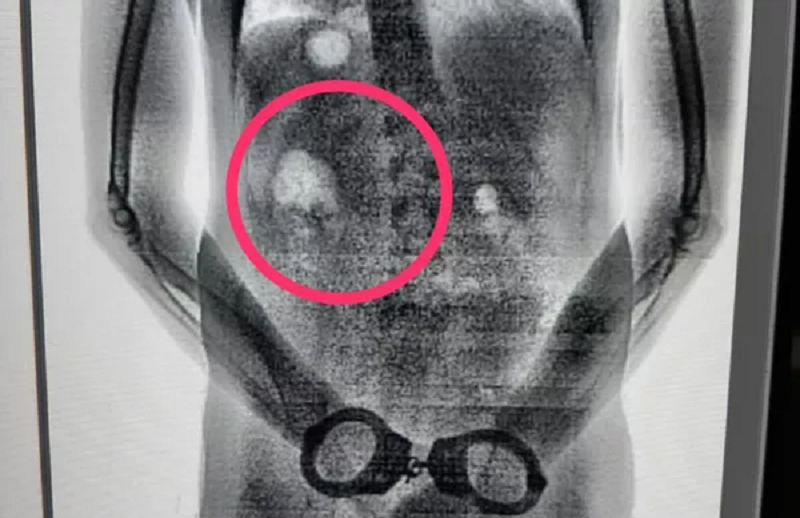

Detentos são flagrados tentando entrar em presídio com tabletes de maconha no estômago no Pará. — Foto: Reprodução / Seap

Presos tiveram o corpo escaneado após retorno da saída temporária para o Círio de Nazaré, segundo a Secretaria de Administração Penitenciária.

Segundo informações divulgadas nesta quarta, dois presos começaram a passar mal e demonstraram preocupação com a revista. Ambos estavam com cinco papelotes de maconha e cinco de tabaco dentro do estômago.

De acordo com a Secretaria de Administração Penitenciária (Seap), a revista ocorreu na terça (27), quando os presos retornavam da saída temporária do Círio. Os dois foram submetidos aos procedimentos de segurança incluindo a revista no escaneamento do corpo inteiro, que detecta objetos ingeridos, sem remover a roupa ou contato físico.